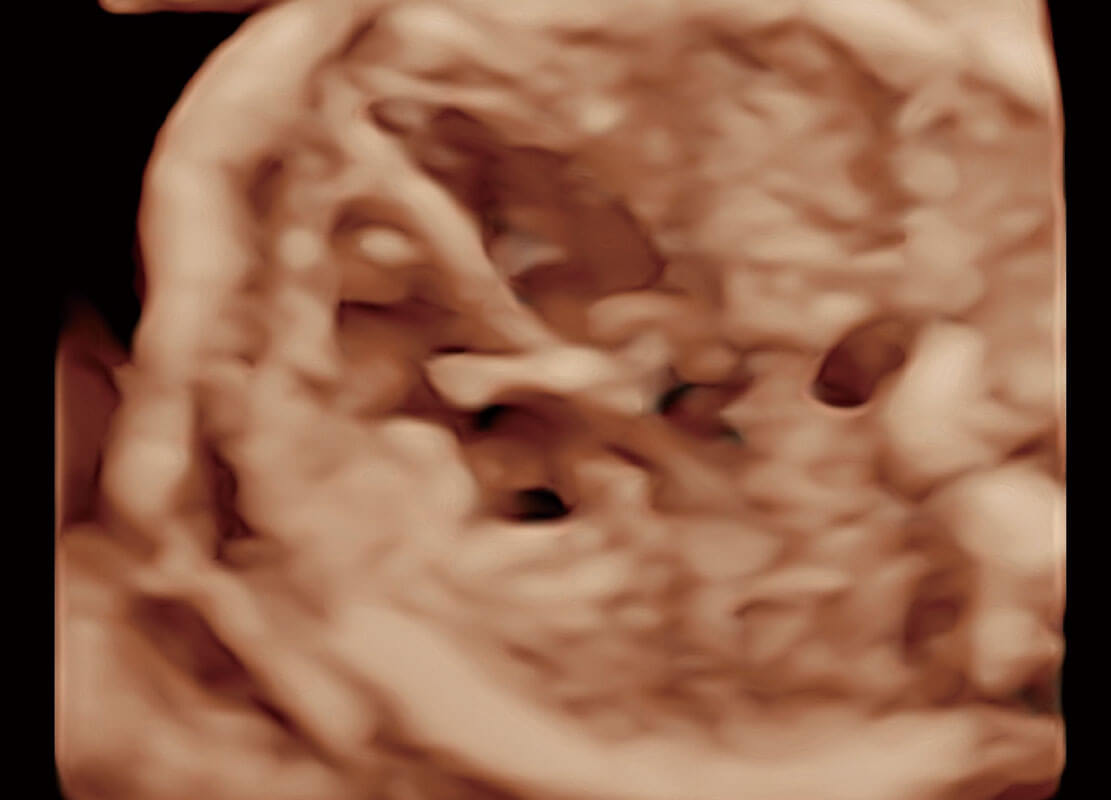

• 腔内三维-宫内节育器

• 腔内三维-光影成像